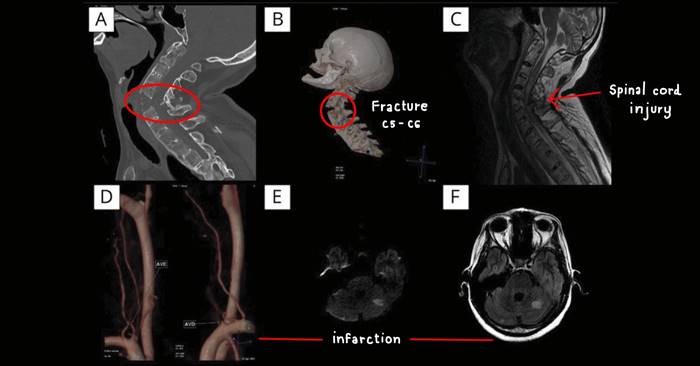

ผู้ป่วยเป็นหญิงอายุ 48 ปี มีอาการปวดคอเรื้อรัง มาพบแพทย์ด้วยอาการอ่อนแรงร่างกายทั่วตัวและปวดคออย่างเฉียบพลัน หลังรับการจัดกระดูก (chiropractic manipulation) ผลการตรวจ x-ray และ MRI พบว่า...

- กระดูกคอส่วน C5-C6 หัก

- มีการบาดเจ็บของเส้นประสาทไขสันหลัง ทำให้เกิดการอ่อนแรงแบบอัมพาตทั้งตัว

- พบการตีบของเส้นเลือดที่ไปเลี้ยงสมองทั้งสองข้าง

- พบการปลิ้นของหมอนรองกระดูก

- พบการฉีกขาดและเลือดออกของเยื่อหุ้มประสาท

ผู้วิจัยได้อภิปรายว่า ผลการตรวจ CT บริเวณกระดูกสันหลังของผู้ป่วยรายนี้ พบว่ามีภาวะ Ankylosing spondylitis ซึ่งถือเป็นปัจจัยสำคัญที่ทำให้กระดูกสันหลังแตกหักได้ง่าย และแน่นอนว่าก่อนทำการจัดกระดูก ไม่มีการตรวจพบภาวะนี้ของผู้ป่วย